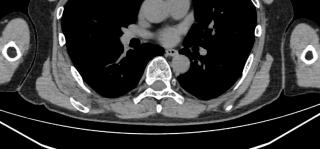

背部弾性線維腫とは、肩甲骨の下側内側にできる、痛みの少ない良性のこぶです。中高年、特に55歳以上の女性に多く、沖縄の離島でよく見られます。肩甲骨と胸壁の間で、繰り返される摩擦や圧力が原因で、線維と脂肪が層のように重なったような組織ができると考えられています。MRIでは筋肉と同じ濃さに見えながら、中にレース状の脂肪が混じる特徴的な模様が現れます。大きくなっても動かしにくくなることは少なく、痛みがなければそのまま様子を見ます。悪性にはならず、自然に消えることもありませんが、放置しても問題ない病気です。

触診、CT、MRI、超音波断層撮影で肩甲骨に接するような腫瘤を認めます。発生する場所や腫瘤の形態から診断します。MRIの所見は筋肉とおなじ吸収域を示し、内部に脂肪が混在します。